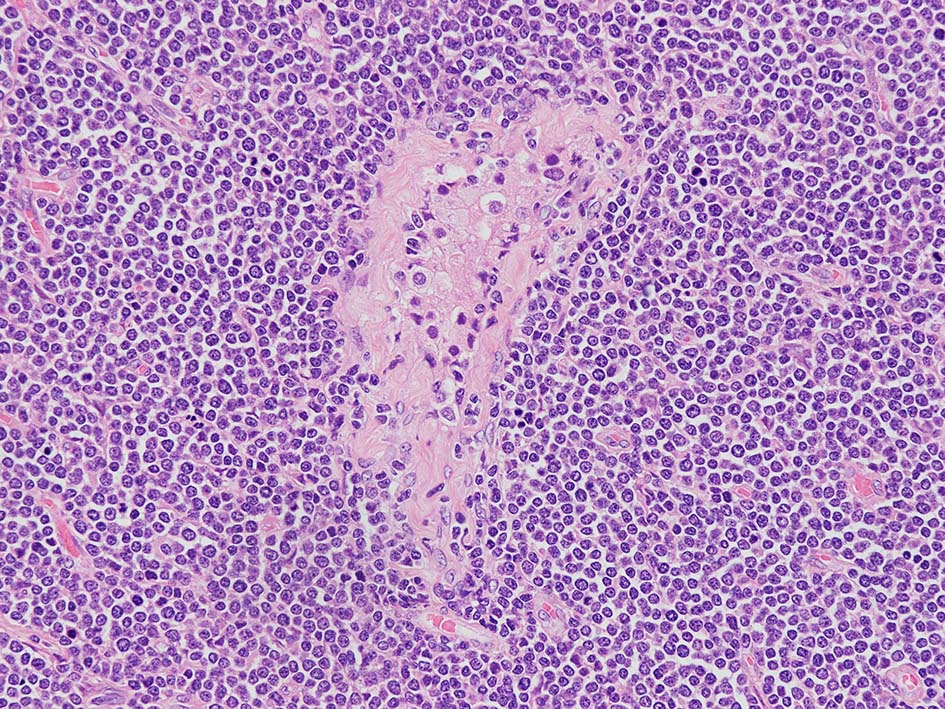

loupe像Aの領域: 精細管をスペアするように, 小型リンパ球優位, 一部中型のlymphoid cellsがシート状密に浸潤増殖する. tubulesのほとんどにはlymphoid cellsが浸潤していないが, LELに似たようなlympho-tubular lesionが少数認められた. x400高倍率では, 増殖細胞は, 粗く, 凝集したクロマチンをもつ類円形, non-cleavedな核をもつ細胞質の乏しいlymphoid cellsである. 核小体か凝集したクロマチンかわかりにくい.

白膜には密に腫瘍性リンパ球が浸潤増殖し, 肥厚, 一部は上図loupe像のように, 腫瘤を形成している. 浸潤リンパ球は精巣実質内よりも, やや大きく, 多稜形, くびれのある核をもち, クロマチンは淡明で核小体が明瞭になってきている.